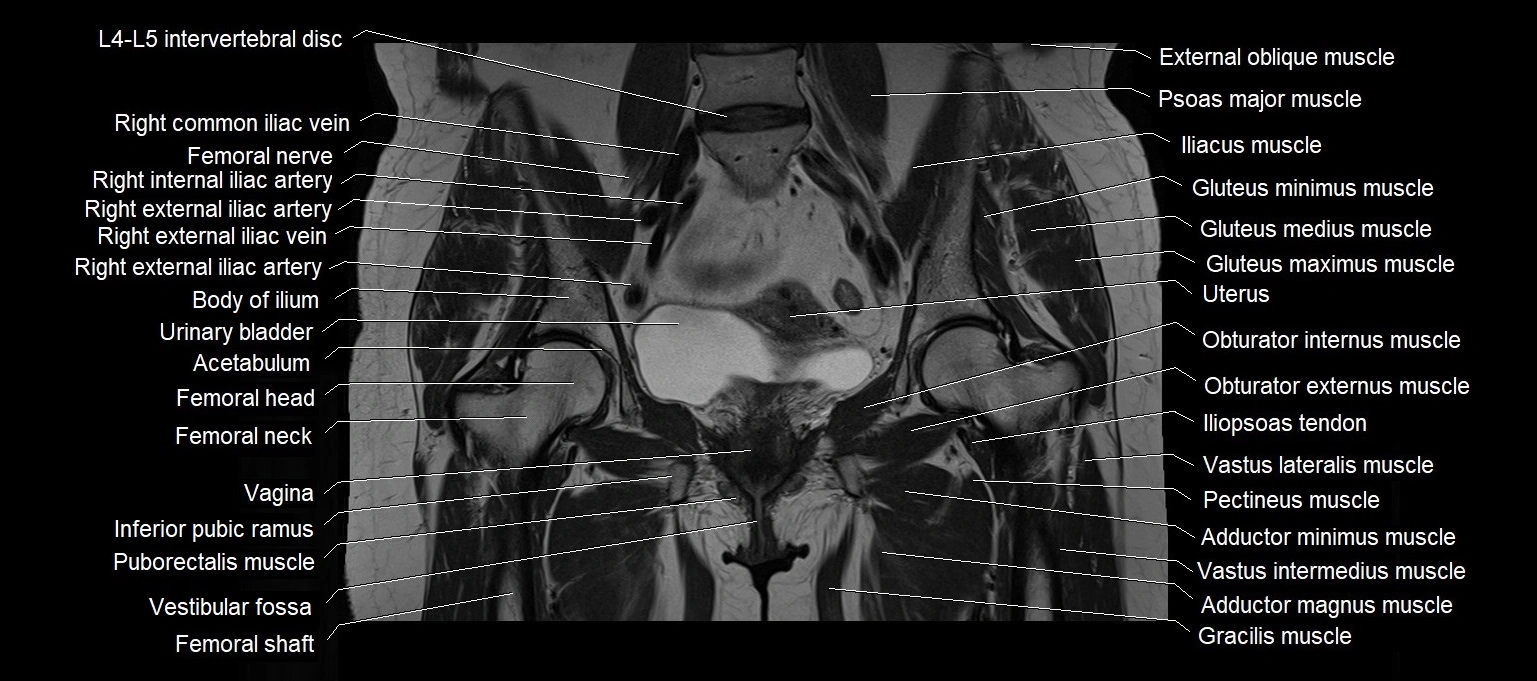

MRI images